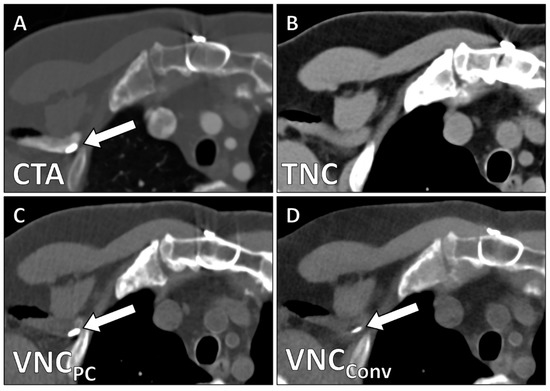

| TNC | VNCPC | VNCConv | Friedman X2 | p | Subgroup Analysis | p | |

|---|---|---|---|---|---|---|---|

| CT values/HU | 44.4 ± 15.5 | 39.1 ± 15.8 | 33.2 ± 15.9 | 19.6 | 0.006 | TNC/VNCPC TNC/VNCConv VNCPC/VNCConv | 0.013 <0.001 <0.001 |

| Noise/HU | 14.9 ± 7.1 | 16.7 ± 7.1 | 18.6 ± 5.3 | 22.8 | 0.003 | TNC/VNCPC TNC/VNCConv VNCPC/VNCConv | <0.001 <0.001 0.021 |

| SNR | 3.3 ± 1.6 | 2.5 ± 1.3 | 1.9 ± 0.9 | 25.0 | <0.001 | TNC/VNCConv TNC/VNCConv VNCPC/VNCConv | <0.001 <0.001 <0.001 |

| Image Quality | 4.2 ± 0.9 | 0.68 (0.44–0.78) | 2.5 ± 0.6 | 0.62 (0.43–0.77) | <0.001 |

| Calcium Subtraction | 4.6 ± 0.5 | 0.75 (0.66–0.82) | 3.0 ± 0.6 | 0.58 (0.40–0.71) | <0.001 |

| Stent Subtraction | 4.7 ± 0.7 | 0.72 (0.58–0.81) | 3.8 ± 1.2 | 0.62 (0.49–0.77) | 0.003 |

| Contrast Subtraction Aorta | 5.0 ± 0.0 | 1.0 (1.0–1.0) | 5.0 ± 0.0 | 1.0 (1.0–1.0) | 1 |

| Contrast Subtraction Total | 4.3 ± 0.8 | 0.86 (0.71–0.95) | 4.0 ± 1.1 | 0.79 (0.66–0.89) | 0.091 |